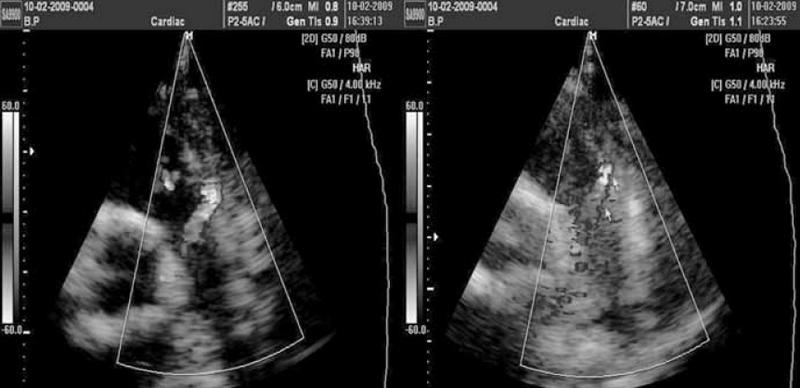

В подавляющем большинстве случаев сброс крови из аорты в легочную артерию через ОАП визуализируется в стволе легочной артерии как поток красного спектра, направленный к датчику в левой парастернальной позиции по короткой оси (см. рис. 2). Сложности эхокардиографической диагностики и дифференциальной диагностики ОАП у детей могут быть обусловлены наличием других разнонаправленных потоков, визуализируемых в стволе легочной артерии, особенно в режиме цветового допплеровского картирования (рис. 3–6). Часть из них направлена «к датчику» и окрашивается в красные цвета, другие направлены «от датчика» и визуализируются как потоки синего цвета. Таким образом, высокоскоростные патологические потоки из аорты в легочную артерию через открытый артериальный проток и аортолегочную фистулу имеют направление «к датчику» и окрашиваются в цвета красного спектра. Низкоскоростные потоки из бассейна коронарных артерий в легочную артерию через коронарные фистулы чаще окрашиваются в синие цвета «от датчика» (см. рис. 3–5).

Рис. 3. Эхокардиограммы выполнены из левого парастернального доступа по короткой оси. В зоне интереса ствол легочной артерии в режиме цветного допплеровского картирования. Слева и справа визуализируется поток из коронарной фистулы (предположительно бассейн левой коронарной артерии) в ствол легочной артерии. При цветном допплеровском картировании аномальный поток окрашен в синий цвет, движение «от датчика»

Рис. 4. Эхокардиограммы выполнены из левого парастернального доступа по короткой оси. В зоне интереса ствол легочной артерии в режиме цветного допплеровского картирования. Слева визуализирована зона бифуркации ствола легочной артерии на правую и левую ветви. На правой эхограмме визуализируется поток из коронарной фистулы (бассейн левой коронарной артерии) в ствол легочной артерии. При цветном допплеровском картировании аномальный поток окрашен в синий цвет, движение «от датчика»

Рис. 5. Эхокардиограммы выполнены из левого парастернального доступа по короткой оси. В зоне интереса восходящая аорта и ствол легочной артерии в режиме цветного допплеровского картирования. Слева визуализирована фистула небольших размеров между аортой и стволом легочной артерии. На правой эхограмме визуализируется поток через фистулу/свищ из аорты в ствол легочной артерии

Диастолический сброс крови через коронарную фистулу в легочную артерию при постоянно-волновом допплеровском картировании отчасти напоминает аналогичный сброс через ОАП, однако является более низкоскоростным и менее продолжительным по времени, не занимая весь диастолический промежуток на допплерограмме (см. рис. 6).